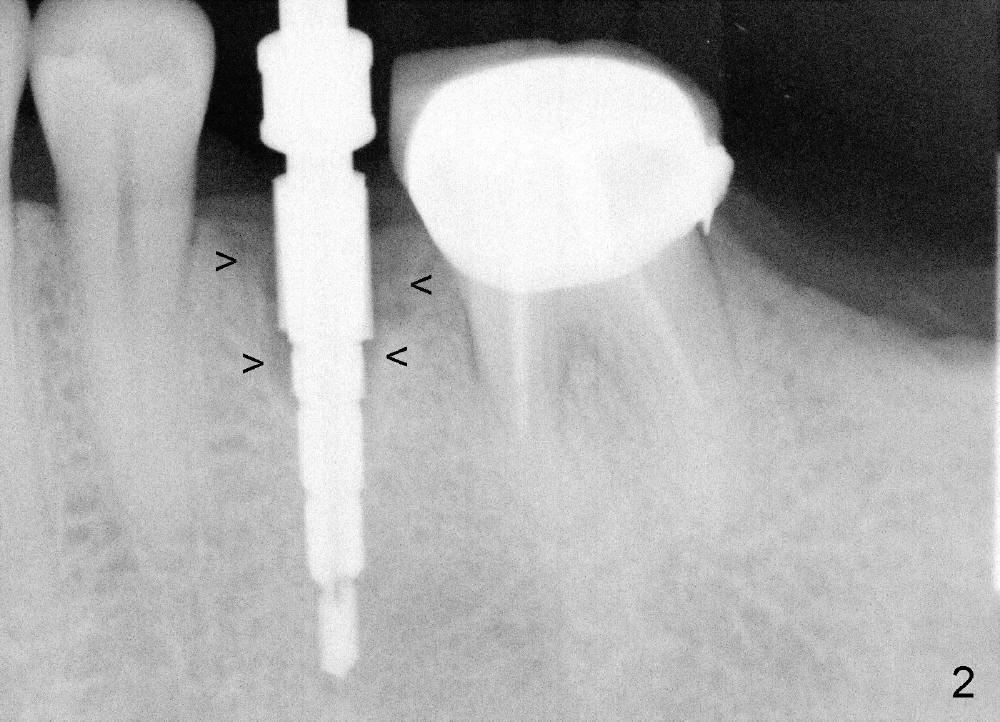

A 44-year-old lady has poor dentition. The tooth #20 has a residual root (Fig.1 R). Immediately after extraction, osteotomy is formed by drills (Fig.2: 3.5x17 mm); a 4.5x17 mm implant is placed (Fig.3 (arrowheads: boundary of the socket)). The patient returns 9 months later with increased radiolucency around the implant (Fig.4) and buccal swelling (Fig.5, asymptomatic). Raising the buccal flap confirms bone loss around the implant (Fig.6). Following debridement, allograft is placed. The source of the infection is unknown.